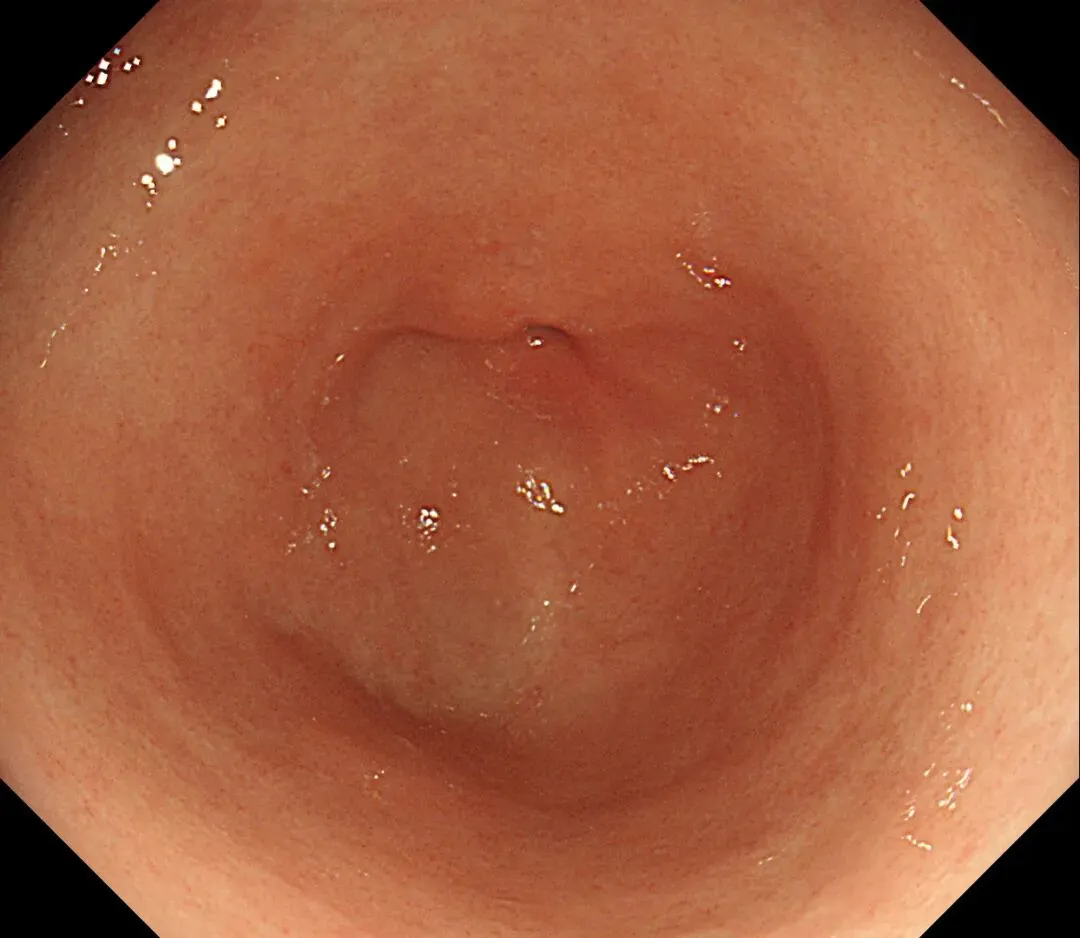

这一期不用码字,挺好的,很可惜一直没机会听过胡导讲的关于这个“花环征”的大课,学习内容来源于雨夜大师的号花环征:AIG背景的胃食管结合部的黄色颗粒状隆起及半透明“泡状”改变

补充自己在两例A型胃炎/AIG 观察到的“花环征”,巩固下学习效果。。。

case2:(made in china机子)👇

1.白光表现为胃食管交界处黄色颗粒状隆起及半透明“泡状”改变

2.窄带光下可见颗粒状隆起呈褐色改变,放大可见细微网状血管结构及半透明“泡状”改变

3.典型病理是鳞状上皮局灶性变薄及黏膜固有层显著增生、扩张的贲门腺。